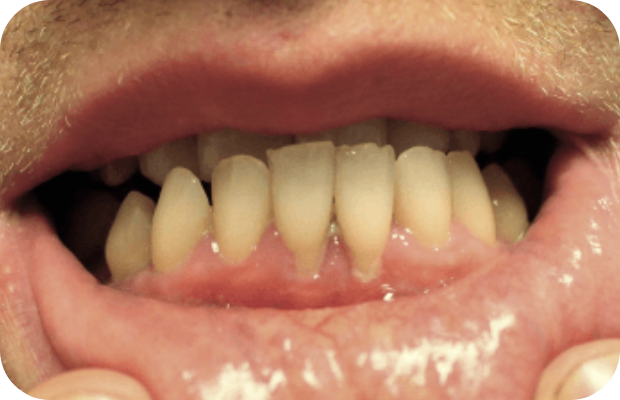

PLGD-1 lesion image gallery

Images of ligneous lesions in real patients with PLGD-1

2. Sadasivan A, Ramesh R, Mathew DG. Ligneous periodontitis in a patient with type 1 plasminogen deficiency: a case report and review of the literature. Case Rep Dent. 2020;2020:5680535.